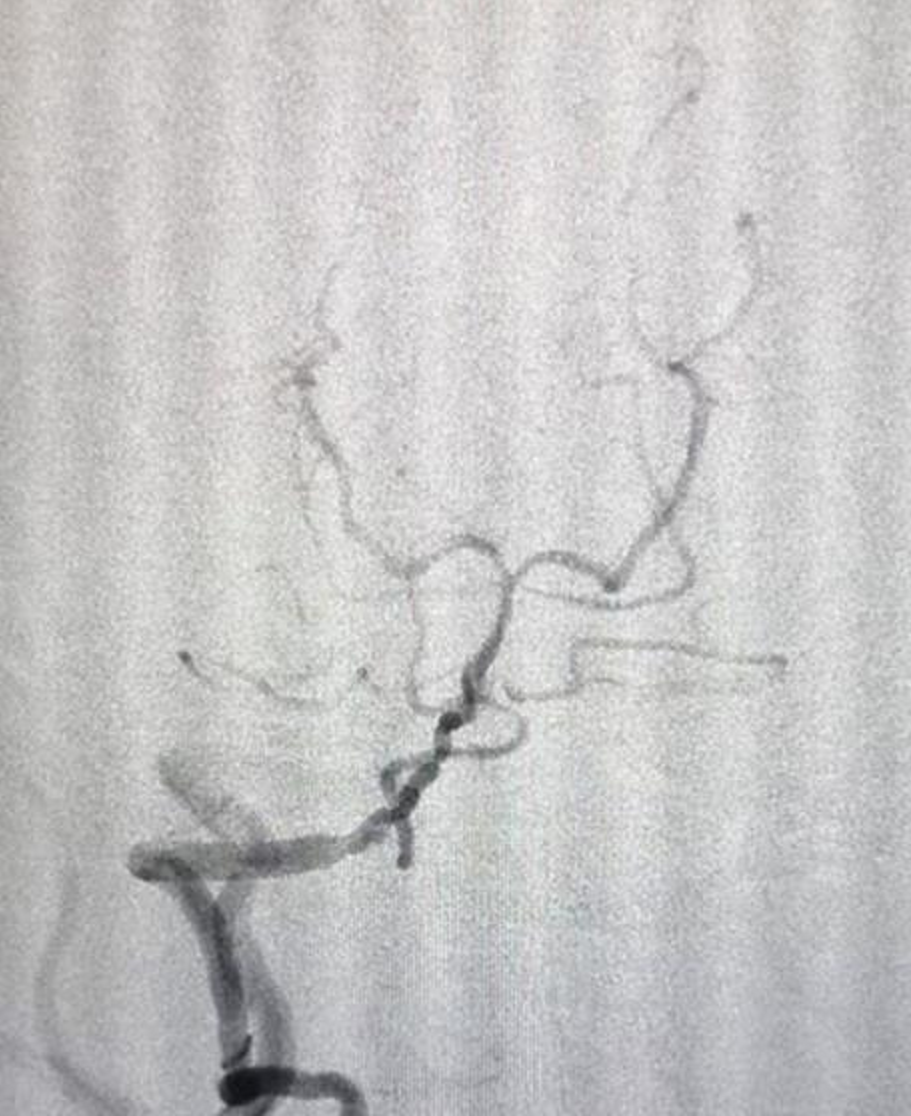

取栓术后造影显示基底动脉远端及双侧大脑后动脉显影

得到患者及家属同意后,团队争分夺秒地抢救,经过2个小时的努力,及时在介入室成功为患者完成取栓,即刻造影显示基底动脉及双侧大脑后动脉血流恢复通畅,患者转危为安,术后已清醒,且左侧肢体肌力较前明显好转。